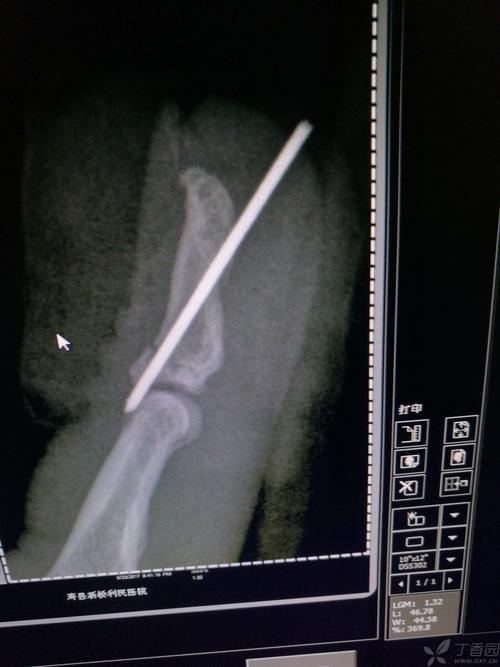

手指食指骨折手术三个月了,外露克氏针还拆不了

克氏针怎么取出来 取克氏针走医保

克氏针怎么取出来

克氏针取出

外露克氏针取出

克氏针内固定术